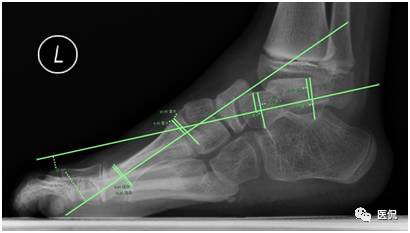

在提供的X线负重侧位图像上,关于角度的测量,下列正确的是(多选)

A 跟骨倾斜角的测量:跟骨下缘的连线、跟骨后结节低点与第五跖骨远端低点的连线,二者的夹角

B 跟骨中轴线的测量:与跟骨倾斜角的测量一致

C 距骨中轴线的测量:距骨距舟关节的中点与过滑车横断面的中点的连线

D 距骨中轴线的测量:距骨头低点与过滑车横断面低点的连线

E 第一跖骨中轴线的测量:第一跖骨近端与远端中点的连线

答案解读:A B E

解析:根据国外最新标准,在原有标准基础上略有修改,更能准确客观的进行数据的测量,测量如下(以左足为例):如下图。

测量数据说明:测量的数据可反映病理改变及其程度,用以下角度加以说明。一是跟距角明显变小(正常值25-45度),严重者跟骨与距骨接近平行;二是跟骨倾斜角变小(正常值17-32度);三是距骨与第一跖骨向上成角,且大于4度。关于角度的测量,中轴线的定位尤为重要,不准确也会影响最终诊断。根据国外最新标准在原有标准基础上略有修改,更能准确客观的进行数据的测量,测量方法见后文。